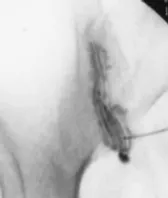

Схематическое изображение лечебно-диагностического введения смеси лекарственных препаратов в крестцово-подвздошное сочленение и рентген-контроль с контрастом.